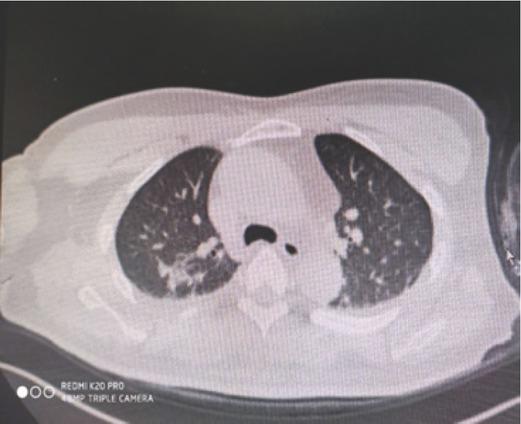

Lung CT performed on 24 October 2019, seven days after the accident, showing a few regions of inflammation in both lungs, fibrous foci, a small amount of effusion in the bilateral pleural cavity, and swelling of adjacent pulmonary tissue

After administration of anti-tetanus immunoglobulin, the wound (Figure 1) was treated again by repeated rinsing with iodophor and saline and covering with antibacterial dressing. An intravenous infusion was initiated to maintain water-electrolyte balance and provide antibiotic treatment with cefoperazone/sulbactam and moxifloxacin. The patient also received daily intravenous infusions of 200 mg methylprednisolone as pulse therapy. Considering the large area of the burn and the long time during which monochloroacetic acid was absorbed, bedside continuous veno-venous haemofiltration (CVVH) was applied every other day to rapidly remove acid from the circulation and prevent acute renal failure. Patient’s lethargy gradually improved, and the level of consciousness returned to normal on the third day of treatment. The wound dressing was changed daily, and the patient did not have severe acidosis, oliguria, or anuria. However, he developed a cough with purulent yellow sputum and his temperature rose to 38.8 °C but dropped to normal after the administration of antibiotics. Six days after the admission (on 24 October), the patient’s condition was relatively stable, and laboratory tests improved (Table 2). Wheezing, coughing, and expectoration continued, however. Figure 2 shows the head, abdomen, and chest scan (Figure 2) revealed cerebellar infarction, a few ischemic degeneration foci in the brain, a few inflammation areas in both lungs, fibrous foci, a small amount of effusion in bilateral pleural cavity, and adjacent pulmonary tissue swelling, indicating monochloroacetic acid aspiration pneumonia. The patient therefore continued to receive antibiotics and started a regular terbutaline atomisation therapy to help expel the phlegm, and the patient was encouraged to cough out the sputum.